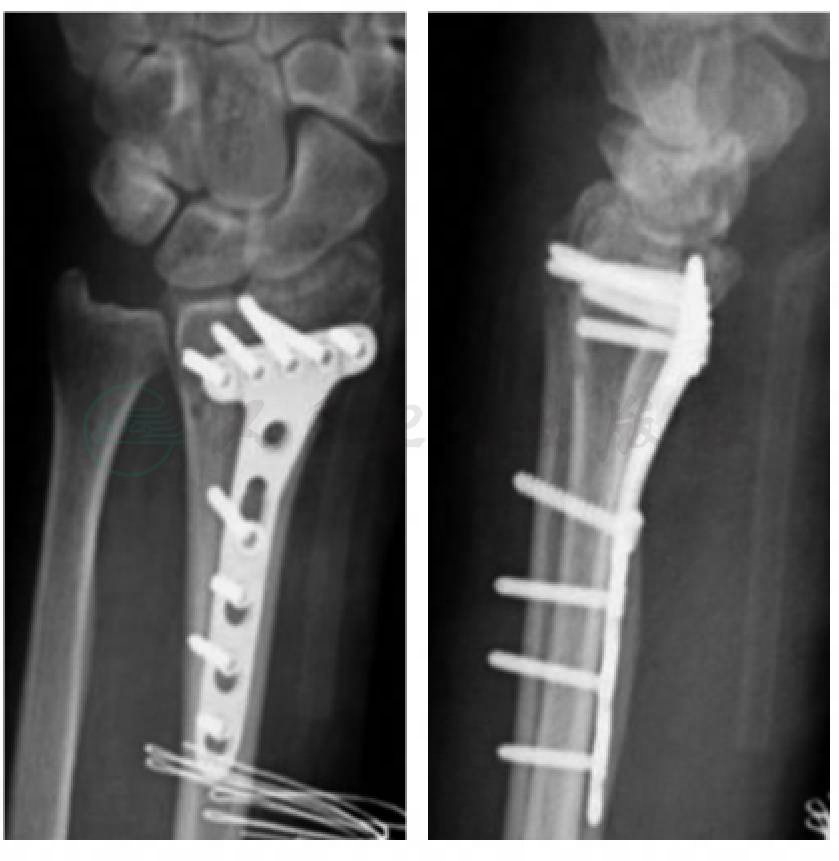

患者术后第1天开始手及腕关节的屈/伸活动,术后第7天进行握力锻炼。此后逐渐加强手的屈伸功能,腕关节屈伸、尺偏、桡偏、旋转及前臂旋转功能练习。术后8个月取出内固定物时,腕关节无疼痛,握力良好,关节功能良好,Gartland及Werley评分优,患者满意(图3,图4)。

图3 术后腕关节正侧位X线片